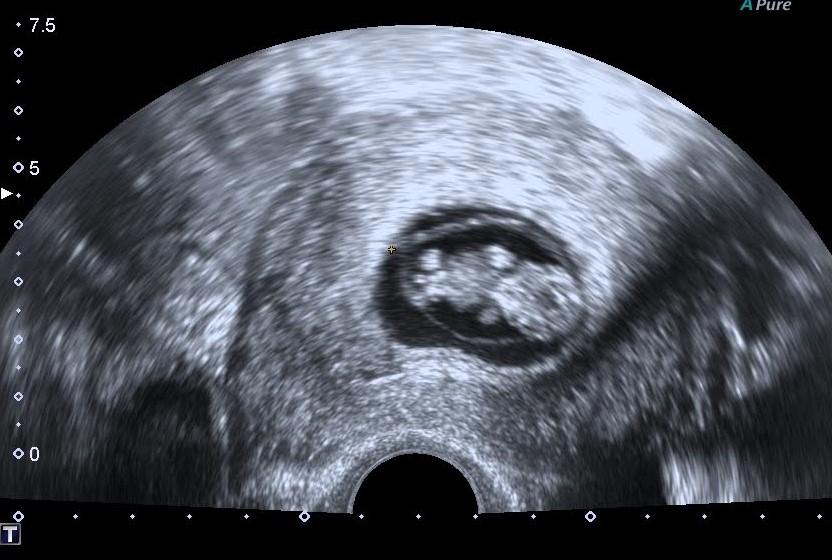

@terka228 Já bych sice byla ráda pyšná teta, že jako zabral ten gelík...ale obávám se, že větší zásluhu bude mít ten progesteron. 😀 Ale je fajn, že jsi se odhodlala k té dr a něco se změnilo a změnilo k o moc lepšímu 🙂 Dělá mi to velikou radost. Jinak teda já už nemám fazolku, ale medvěda 🙂 Takhle si tam lebedí 🙂 A co Ty a příznaky? Jak jsi na tom? Žaludek? Únava? Nebo zatím všechno v pohodě?

@evzenie2016 jéééé to je krásné🙂) vypadá jak medvídek, to jo=)) ❤

@evzenie2016 Ježíš, to je nádherný medvídek !!!!❤❤❤ Taky se na takovou fotečku těším, ale ještě měsíc musím počkat 🙂 Jinak spíš jen únava a někdy trochu cítím podbřišek..hnědý výtok zmizel ( ťuk, ťuk, ťuk )🙂 Dnes jsem teprve 5+0. Už jsem si ale koupila ten superfolin 1, protože mi došli vitamíny... Za týden na utz, to budu 6+1. Myslíš, že už bude vidět srdíčko???